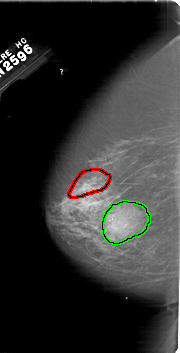

A_1666_1.LEFT_MLO

FILE: A_1666_1.LEFT_MLO.OVERLAY

TOTAL_ABNORMALITIES 1

ABNORMALITY 1

LESION_TYPE CALCIFICATION TYPE PLEOMORPHIC DISTRIBUTION SEGMENTAL

ASSESSMENT 4

SUBTLETY 3

PATHOLOGY MALIGNANT

TOTAL_OUTLINES 1

BOUNDARY

ABNORMALITY 2

LESION_TYPE MASS SHAPE OVAL MARGINS OBSCURED

ASSESSMENT 3

SUBTLETY 5

PATHOLOGY BENIGN_WITHOUT_CALLBACK